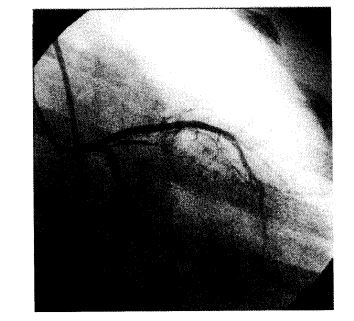

Infarto agudo de miocardio con shock cardiogénico por oclusión completa del tronco de la arteria coronaria izquierda y síndrome de respuesta inflamatoria sistémica. Presentación de dos casos

La oclusi6n aguda del tronco de la arteria coronaria izquierda se ve solamente en el 0,37% de los infartos de miocardio estudiados mediante coronariografías. La sobrevida de estos pacientes parece que depende de las características anatómicas de su árbol coronario y de la precocidad con que se logre repermeabilizar la arteria. Los dos pacientes que presentamos fueron reperfundidos mediante angioplastía primaria; uno a los 5 minutos y el otro a las 2 horas del evento oclusivo. A pesar del éxito primario, la recuperación de la función ventricular fue diferente y ambos tuvieron una evolución t6rpida por el desarrollo de un síndrome de respuesta inflamatoria sistémica.